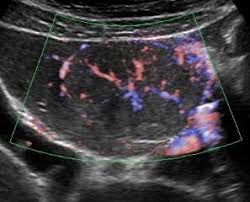

限局性結節性過形成:スポークウイールパターン

限局性結節性過形成(FNH: focal nodular hyperplasia)でよく見られる特徴的な血管パターン。造影超音波検査で血管相が早期に濃染される際に認められ肝腫瘍の中心から放射状に血管が伸びる様子を示し、「車輻様構造」とも表現されます。